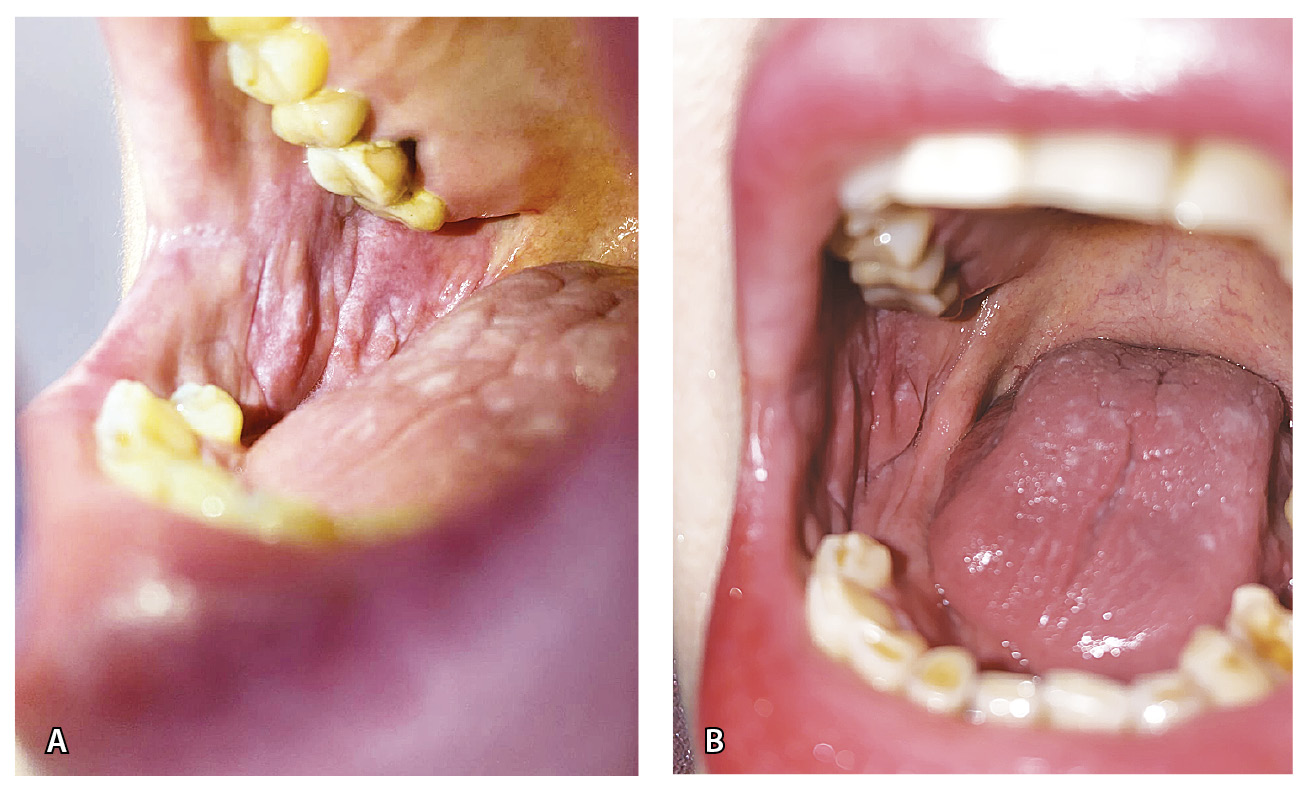

Кожа лица слегка отечна и гиперемирована, лицо имело «лунообразную» форму. На коже туловища в области груди и боковых поверхностей живота отмечались папулы розового цвета, единичные бляшки размером 1,0 × 1,0 см розового цвета с наслоением белых чешуек на поверхности (рис. 1). Феномен псориатической триады отрицательный. На коже волосистой части головы в затылочной области – очаг размером 3,0 × 2,0 см, в центре которого наслоение плотных серебристых чешуек, по периферии – область гиперемии (рис. 2А). На ладонной и боковой поверхности первого и второго пальцев правой кисти – участки гиперкератоза желтого цвета с белыми чешуйками (рис. 3). На коже паховой области, больших половых губ – папулы синюшного цвета, полигональные вытянутые с блеском при боковом освещении. На слизистой больших и малых половых губ, ануса – белесоватые папулы, сливающиеся в бляшки (рис. 4А). На слизистой щек – белесоватые папулы, сливающиеся в ретикулярные бляшки, отдельные белесоватые папулы – на спинке языка (рис. 5). На красной кайме нижней губы в латеральных частях – белесоватые вытянутые бляшки размером 1,0 × 0,5 см. Субъективно пациентка отмечала зуд в области гениталий.

Рис. 5. Лихеноидные высыпания на слизистой оболочке полости рта и языка (правая щека): А – до лечения, Б – после лечения

Через 6 недель после начала наружной терапии отмечена положительная динамика: разрешение высыпаний на слизистой гениталий, пигментные пятна на месте папул на коже паховой области и больших половых губ (рис. 4Б), уменьшение количества высыпаний на слизистой полости рта и языка (рис. 6), разрешение бляшек на красной кайме нижней губы, разрешение центральной части очага в затылочной области (рис. 2Б). Единичные папулы и бляшки на коже туловища и очаги на пальцах кисти сохранялись.

Рис. 6. Лихеноидные высыпания на слизистой оболочке полости рта и языка (левая щека): А – до лечения, Б – после лечения